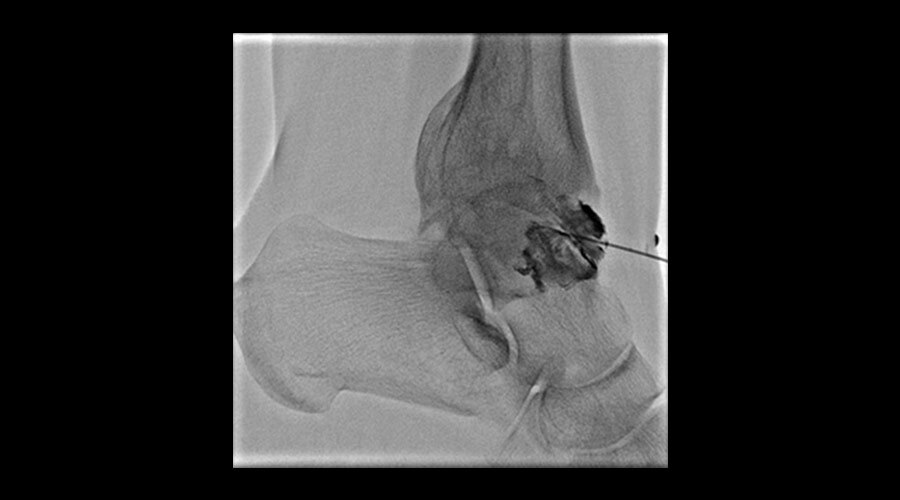

Klinik Görüntüler

-

Elde AVM